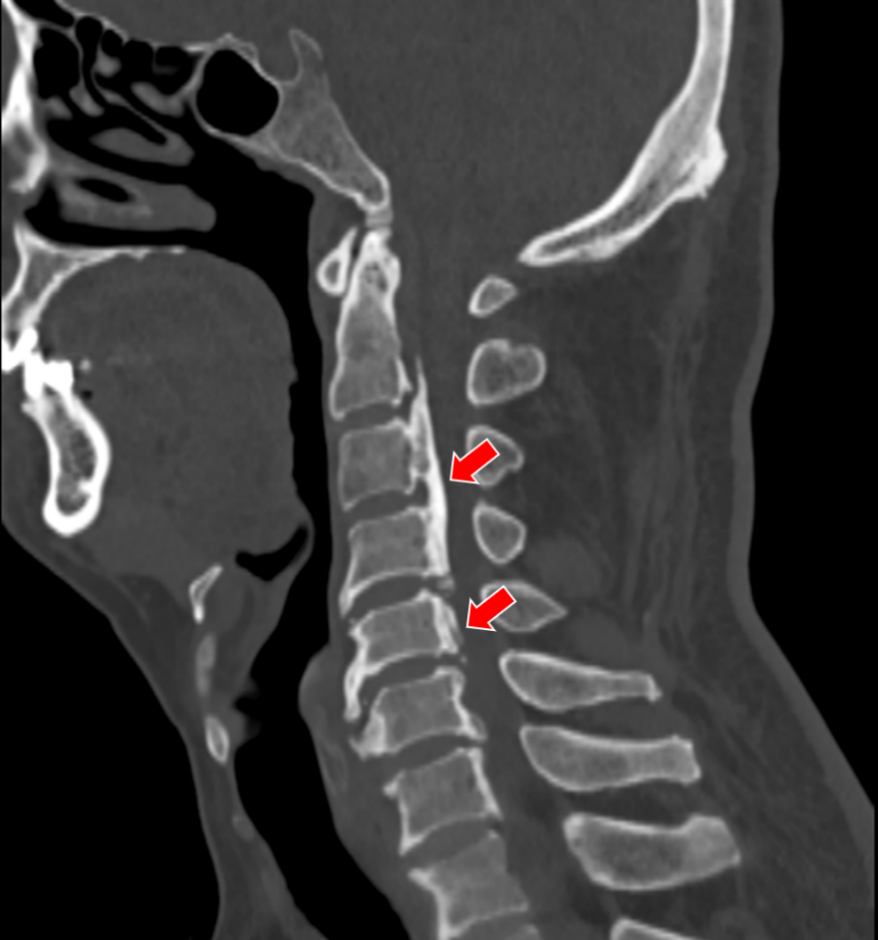

(颈椎CT显示张先生C2-6椎体后纵韧带广泛骨化,椎管狭窄明显)

就在张老爷子术后没几天,他的儿子张先生也住院了,父子俩被特意安排住在同一间病房。84岁老父亲第二次手术的成功给了张先生极大的鼓舞与信心,多年来对手术的恐惧感也减轻了不少。就在父亲术后第八天,张先生也接受了颈椎后路椎管扩大成形术。

术后第一天,他就感觉自己四肢麻木明显缓解,效果可谓立竿见影,这让他喜出望外,坦言早该积极接受治疗。俗话说久病成良医,张先生这些年来对颈椎病的研究可没少下功夫,他知道这种病拖得越久,越不利于康复。他告诉姜主任,等他出院后,一定现身说法,告诉其他病友:得了颈椎病该手术的,一定不要犹豫不决,免得耽误了治疗的最佳时机。